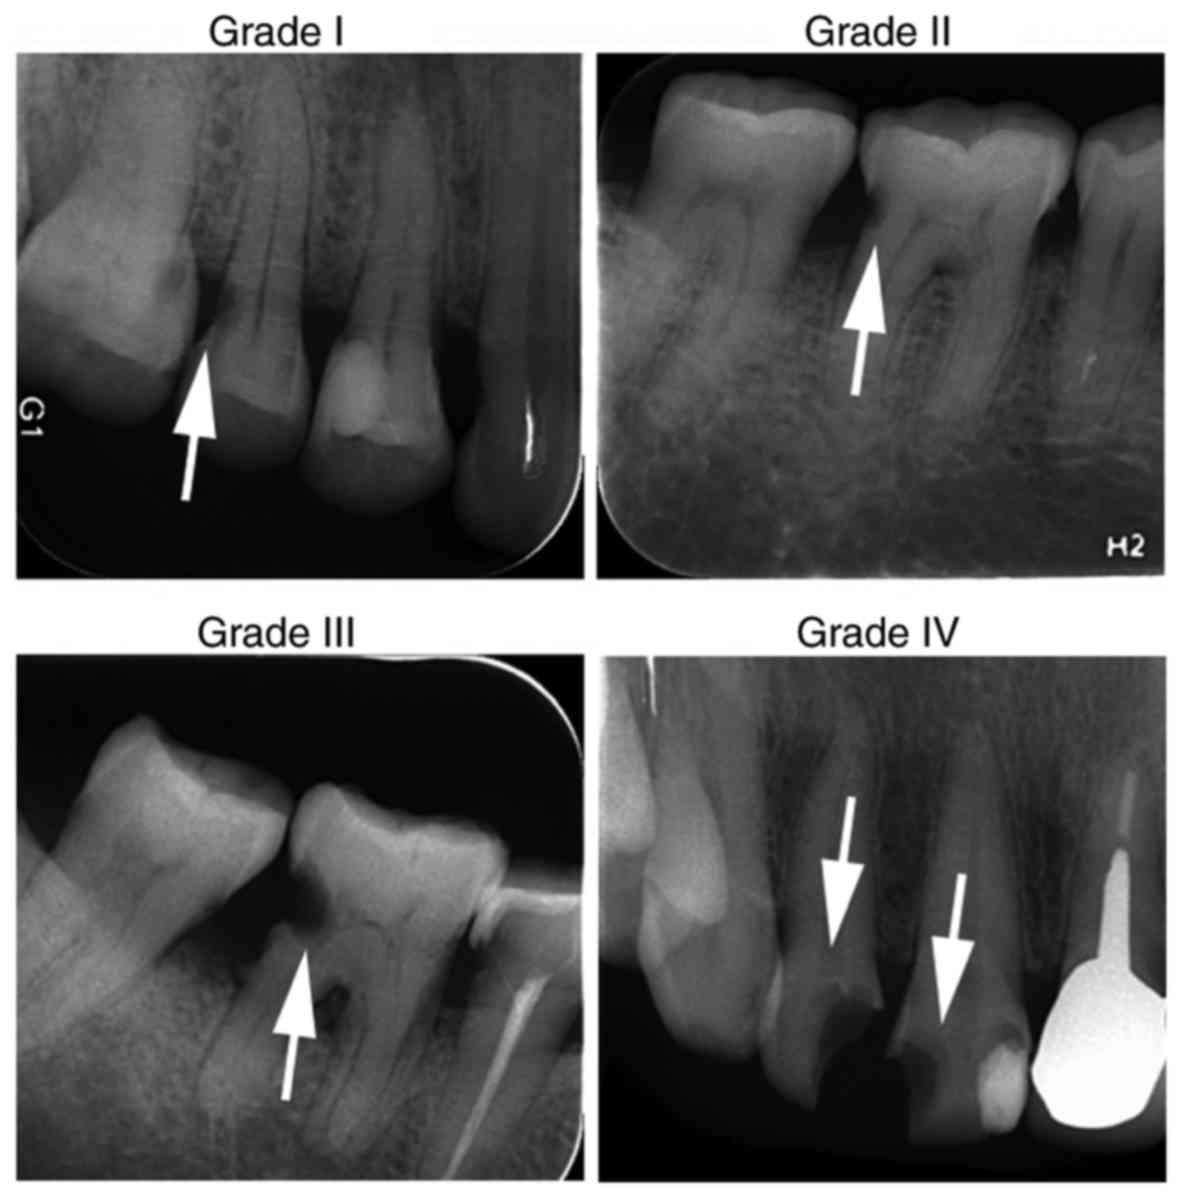

Periodontics 2 Treatment of severe periodontic‑endodontic combined lesionsの詳細情報

Treatment of severe periodontic‑endodontic combined lesions。Effect of Time Lapse between Endodontic and Periodontal。Preparation of an injectable zinc-containing hydrogel with。

「Periodontics2」